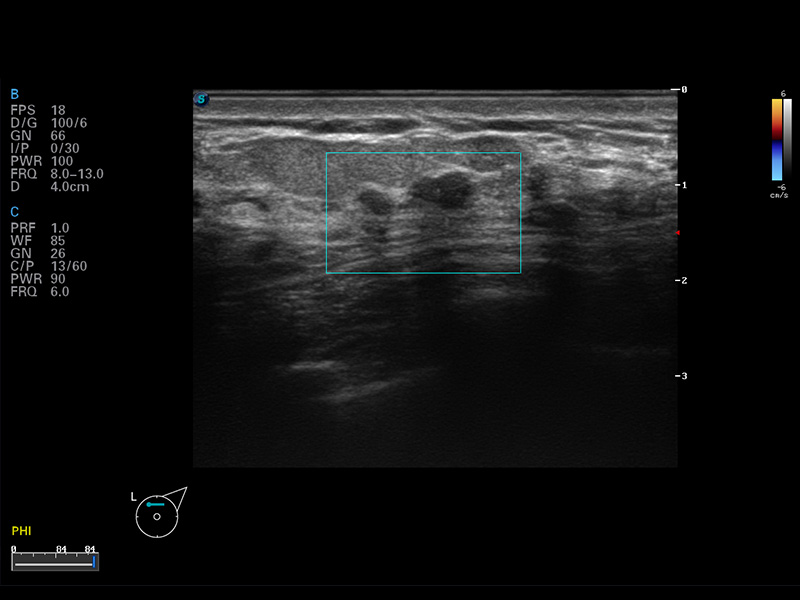

S8 EXP便携式彩色多普勒超声诊断仪是美狮贵宾会官网研发的高端全身应用型便携彩超。高通道的VIS平台融合可视化(Visual)、智能化(Intelligent)和人性化(Smart)的特点,配以美狮贵宾会官网自主研发生产的探头大家族,使您能够快速、准确的获得病人信息,提高工作效率的同时减轻疲劳。

谐波成像